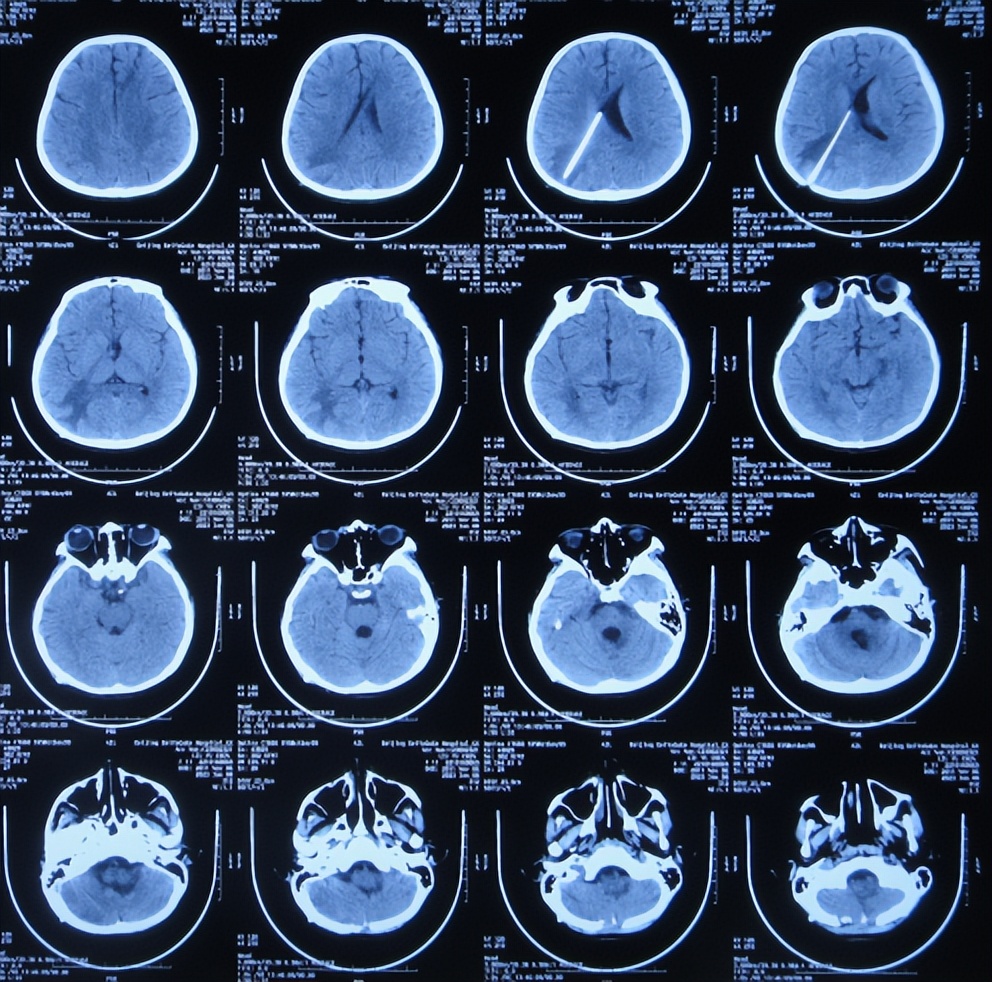

2022年12月12日(住院治疗57天),颅脑CT示脑室引流术后状态( 图-15 ),给予夹闭引流管。

图-15: 2022年12月12日颅脑CT

但夹闭5天后即2022年12月17日,患儿出现不适,查颅脑CT示脑室有扩张( 图-16 ),打开引流管。

图-16: 2022年12月17日颅脑CT

2022年12月20日(住院治疗65天),查头颅CT示脑室缩小( 图-17 ),肺部CT示感染好转( 图-18 )。

图-17: 2022年12月20日颅脑CT

2023年1月9日(住院治疗85天即脑胶质瘤切除术后81天)出院,出院时:意识清楚,头痛恶心完全消失,自己走路不稳( 图-19 );出院时肺部感染变好、颅脑CT示无异常( 图-20 )。

图-20: 出院时颅脑CT